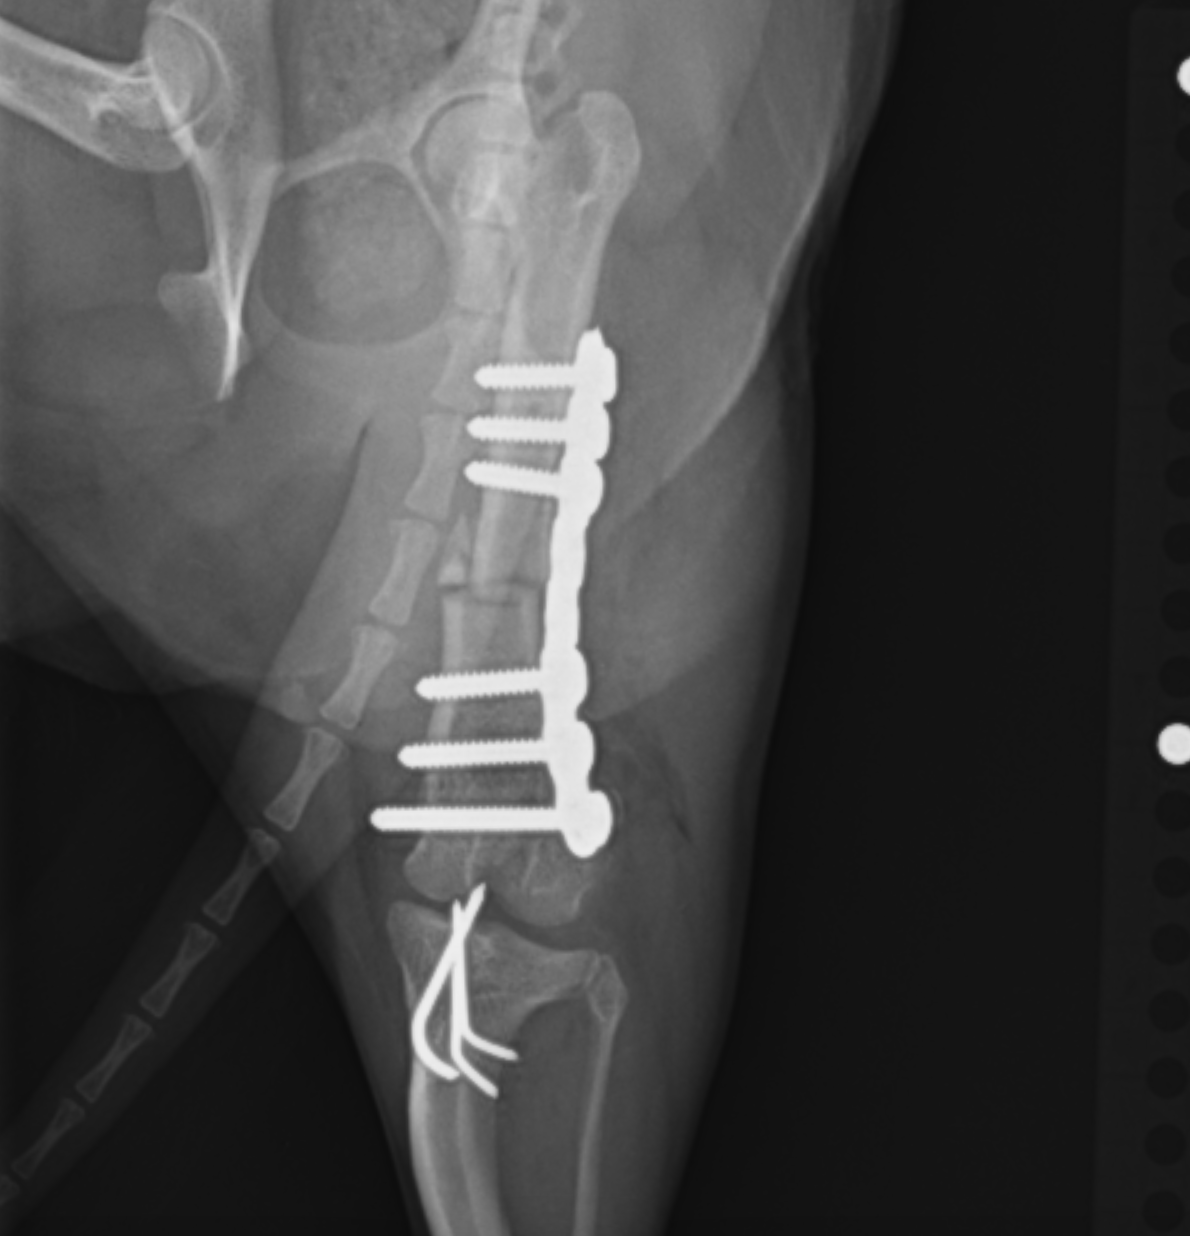

にプラスして大腿骨の矯正骨切術を追加する場合があります。パテラの脱臼に大腿骨の湾曲変形が大きく関わっているからです。この術式の場合には骨の一部を楔形に切断し、プレートで再度固定するという術式を実施します。

大腿骨矯正骨切術:切断した骨と骨をプレートを用いて固定します。術前よりも湾曲が直線に近くなっているのがわかると思います。